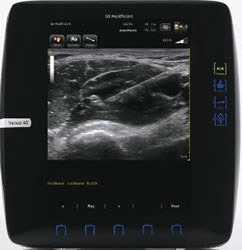

Venue 40 Anesthesiaで撮影した神経ブロック画像